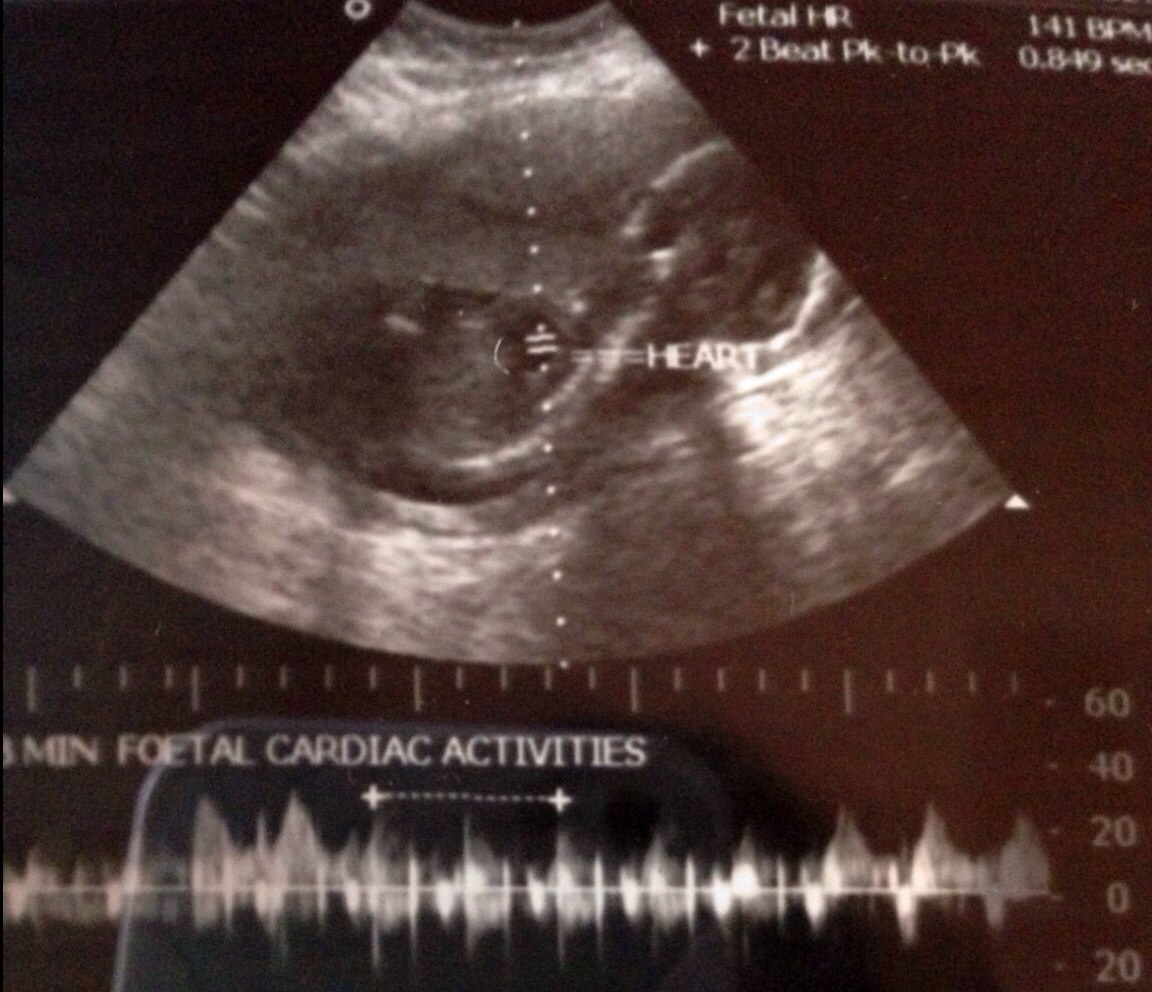

This 20+3 weeks scan. Pls guess the gender!Attachment 14247Attachment 14248Attachment 14249Attachment 14250